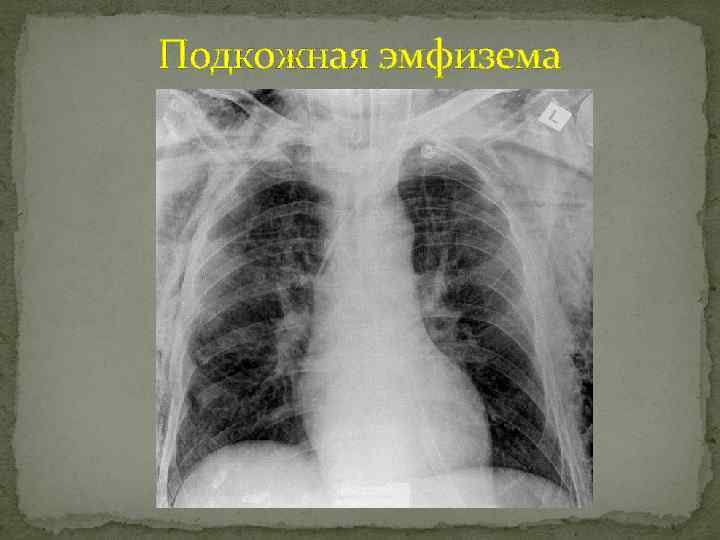

Подкожная эмфизема